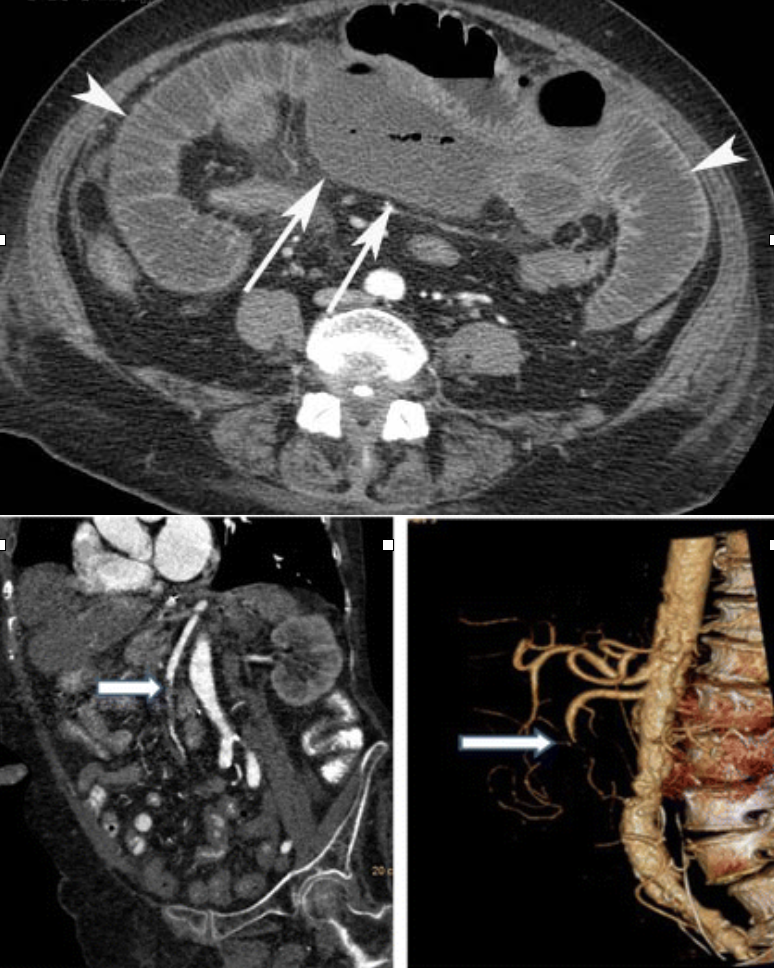

Abdominal aortic aneurysm (AAA)

CTA Abdomen/Pelvis IV contrast

Trauma: Liver

CTA Abdomen/Pelvis IV contrast

Trauma: Spleen

CTA Abdomen/Pelvis IV contrast